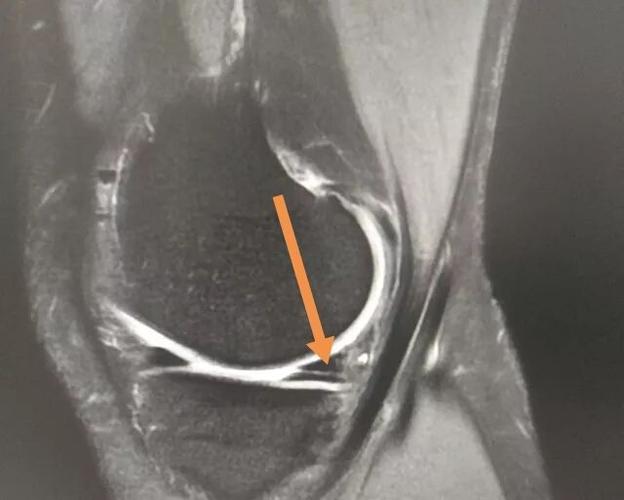

骨科基础丨半月板损伤磁共振表现

半月板损伤磁共振图解

半月板核磁共振图解析

半月板磁共振图解

半月板3度撕裂共振图